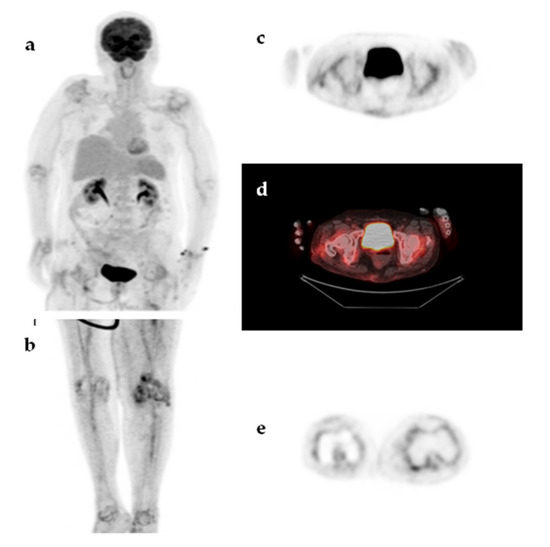

| Undiagnosed fever | 11 (22%) |

| Spontaneous recovery of fever | 7 |

| Recovery of fever with corticosteroids or NSAIDs | 3 |

| Recurrent fever until death | 1 |

| Categories | TP | FP | TN | FN | N |

|---|---|---|---|---|---|

| Infections | 19 | 0 | 0 | 1 | 20 |

| Malignancies | 8 | 0 | 0 | 0 | 8 |

| Non-infectious inflammatory diseases | 9 | 2 | 0 | 0 | 11 |

| Undiagnosed fever | 0 | 4 | 6 | 1 | 11 |

| Total (%) | 36 (72%) | 6 (12%) | 6 (12%) | 2 (4%) | 50 |